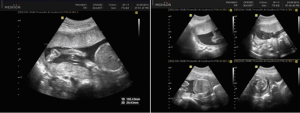

Ecografía Obstétrica de Detalle Anatómico

Ecografía Obstétrica de Detalle Anatómico También llamada Ecografía de Tercer Nivel, comprende de un examen detallado de las estructuras anatómicas fetales, así como la valoración del crecimiento y